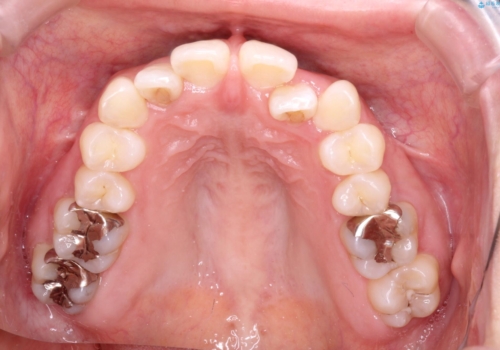

初診時の歯並びの状態としては、上下ともに前歯部の中等度のがたつきがあり、特に左上の前歯が1本内側に入り込んでしまっている状態でした。

また、2mm程度の正中離開がありました。